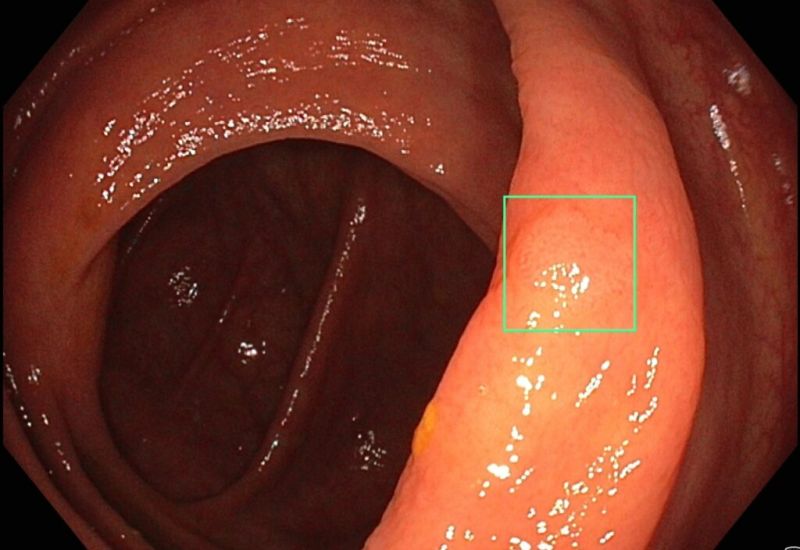

KI unterstützt bei Endoskopien

Wie die neue Technik bei Darmspiegelungen zum Einsatz kommt

Ravensburg – Künstliche Intelligenz (KI) ist in aller Munde. Experten sind sich einig: In der Medizin könnten künftig zahlreiche Bereiche von der modernen Technik profitieren. Schon heute werden computergestützte Software-Systeme eingesetzt, um bei der bildgebenden Diagnostik zu unterstützen. Auch die Klinik für Innere Medizin I am St. Elisabethen-Klinikum um Chefarzt Prof. Dr. Peter Klare verfügt seit Kurzem über eine solche KI-Software, die die Ärzte bei Darmspiegelungen (Koloskopien) nutzen.